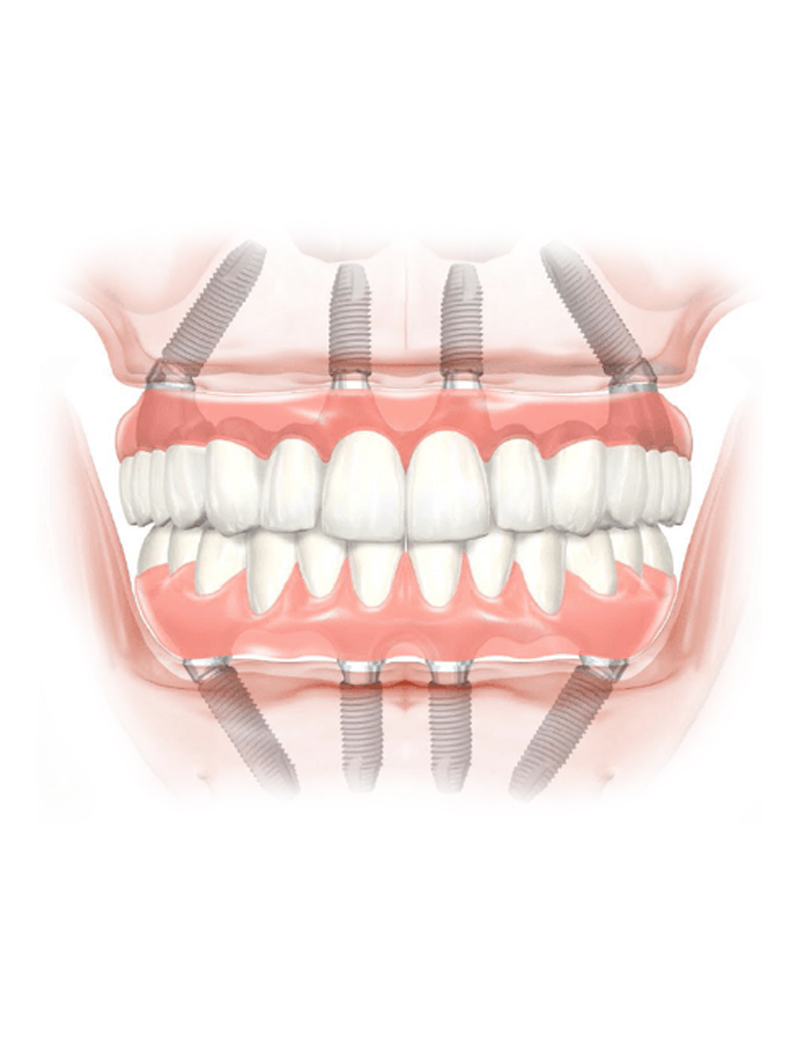

Zygomatic implants

The zygomatic implants are an excellent solution in cases of patients with little jaw bone. In this type of intervention the advantage is to be able to insert an implant without additions or regeneration of jaw bone.

The zygomatic implants also allow patients who do not have a sufficient amount of bone to support a fixed prosthesis and have a stable dentition in a very short time and in total relaxation.

In fact, these implants allow the new fixed denture to be used immediately. They are ideal especially for those completely edentulous patients who have very pronounced atrophy.